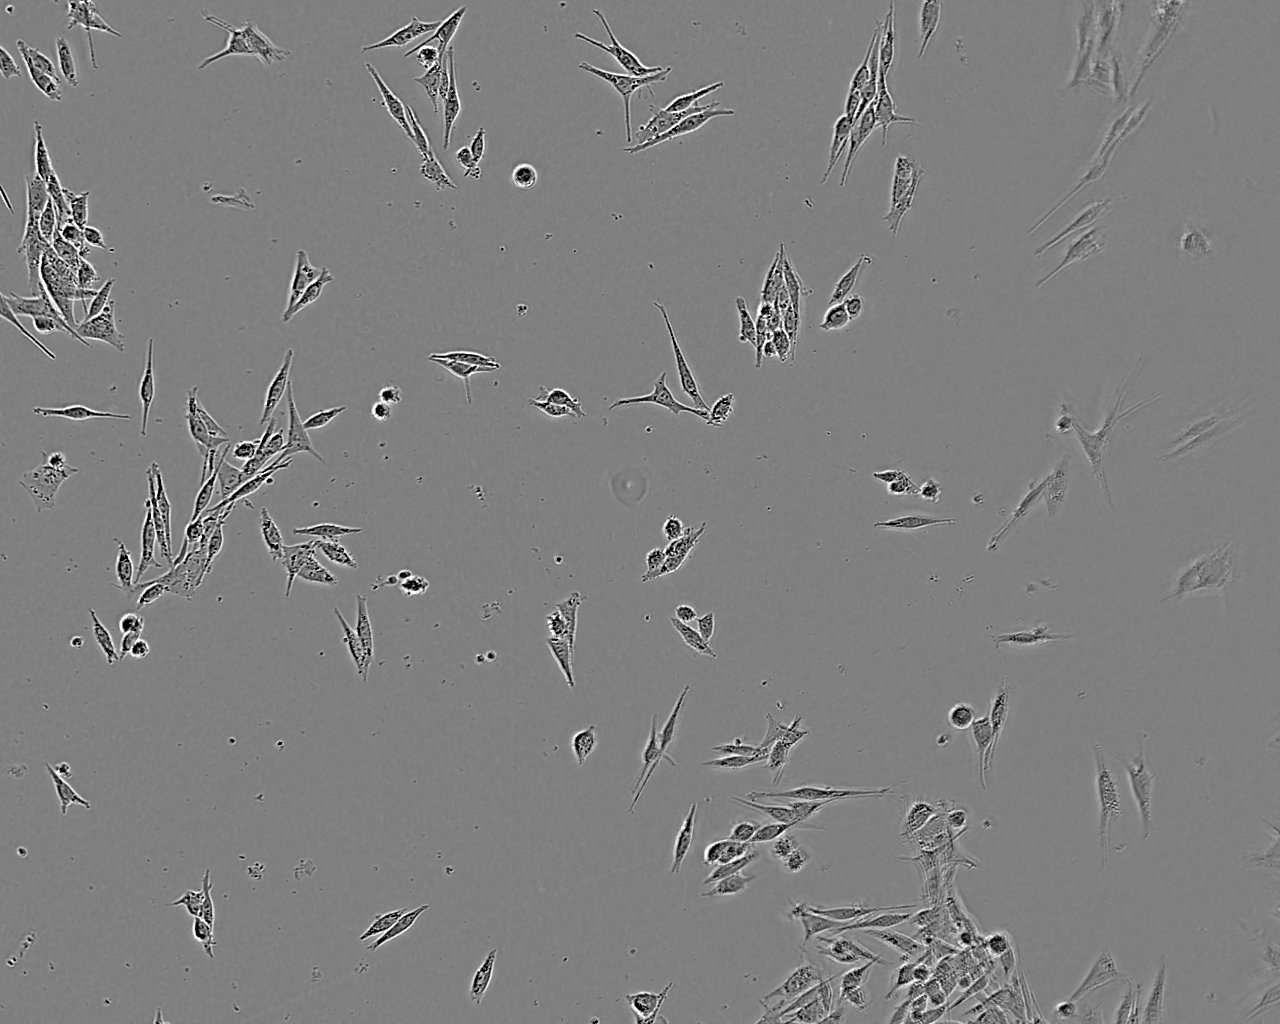

特征特性 从一例原位脉络膜黑色素瘤病例中分离建系。该细胞是ESTDAB计划中收集的超过170株黑色素瘤细胞中的一株

形态特征 上皮细胞样

生长特征 贴壁